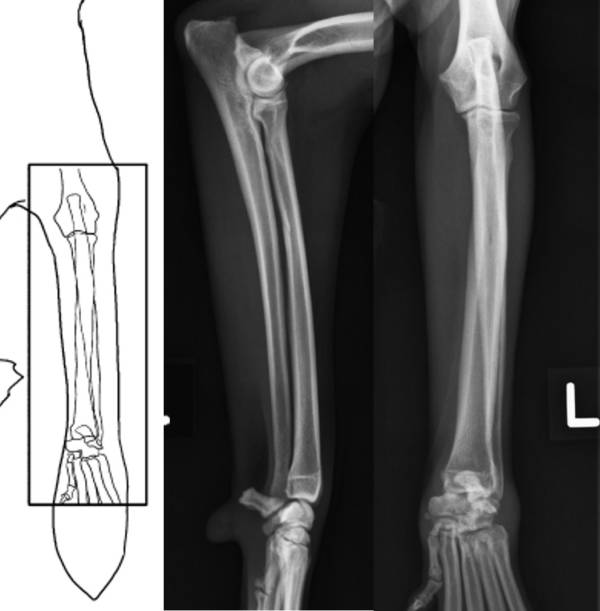

Röntgen Unterarm

Röntgen Unterschenkel